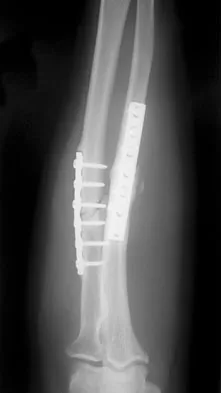

Which of the following choices best describes the fracture pattern shown in Figures 2a through 2c?

Explanation

The fracture pattern shown in the radiographs is a fracture of the posterior column. The only line interrupted on the AP pelvis is the ilioischial line. The obturator oblique view shows that the iliopectineal line is intact as is the outline of the posterior wall. The iliac oblique view shows an interruption of the ilioischial line and an intact anterior wall. Therefore, this fracture is a fracture of the posterior column. Letournel E, Judet R: Fractures of the Acetabulum, ed 2. Berlin, Germany, Springer Verlag, 1993.